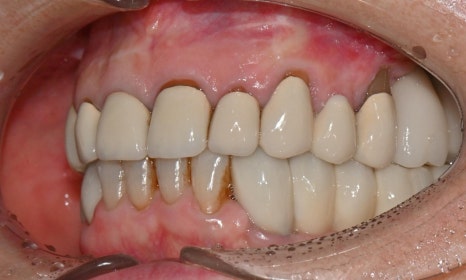

치료 마무리 후 smile 사진 - 연세정원치과

앞니 보철 치료는 단순히 크라운을 새로 만드는 치료가 아니라, 잇몸 상태, 치아의 마모와 위치, 스마일라인, 발음과 식사까지 함께 고려해야 하는 종합적인 치료입니다. 특히 오래된 보철을 교체하는 경우에는 보이지 않던 문제들이 함께 발견되는 경우가 많아, 단계별 계획과 임시보철을 통한 검증 과정이 최종 치료 결과의 정확성과 안정성을 결정짓는 중요한 요소가 됩니다. 이러한 접근을 통해, 심미성과 기능을 동시에 만족시키는 치료 결과를 얻을 수 있으며, 장기적인 유지와 환자 만족도 또한 크게 향상됩니다.

이번 케이스는 임시치아 단계에서 환자분과 충분히 소통하며 디자인을 조정한 덕분에, 기능과 심미를 모두 만족시키는 방향으로 치료를 진행할 수 있었습니다. 특히 앞니는 웃을 때나 말할 때 거의 항상 보이는 부위이기 때문에, 조금만 모양이나 색이 어긋나도 인상이 크게 달라질 수 있으므로, 얼굴과 미소 전체와 조화를 이루는 보철을 만들기 위해 환자분과 충분한 소통을 통해 세밀한 디자인 조정과 단계별 검증을 시행할 수 있었습니다.